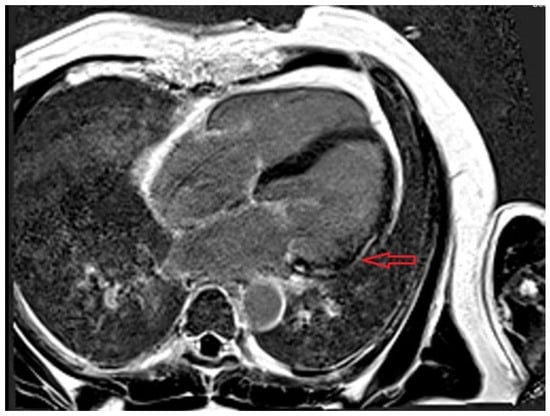

Myocardial and vascular injury secondary to SARS-CoV-2 infection and vaccination has emerged as a clinically relevant phenomenon, with distinct but overlapping mechanisms. Myocardial injury in COVID-19 results from a complex interplay between direct viral effects and immune-mediated inflammation, supported by histopathological studies revealing [...] Read more.

Myocardial and vascular injury secondary to SARS-CoV-2 infection and vaccination has emerged as a clinically relevant phenomenon, with distinct but overlapping mechanisms. Myocardial injury in COVID-19 results from a complex interplay between direct viral effects and immune-mediated inflammation, supported by histopathological studies revealing macrophage-rich infiltrates, microthrombosis, and supporting fibrosis in isolated areas. In contrast, vaccine-associated myocarditis—reported predominantly following mRNA vaccines—has a self-limiting clinical course, with mechanisms likely involving molecular mimicry, aberrant immune activation, or hypersensitivity reactions, although these pathways require further validation. Although mRNA vaccines have been associated with a small increase in myocarditis, particularly in young men, the risk is significantly lower than that associated with COVID-19 infection, and the cardiovascular benefits of vaccination far outweigh these rare adverse events in most populations. After the end of the pandemic, the number of patients with severe forms of COVID-19 has decreased significantly, but we consider that cardiac involvement remains an important issue for the acute and long-term prognosis of patients with SARS-CoV-2 infection. Our paper synthesizes the latest epidemiological and mechanistic evidence on the link between COVID-19, vaccination, and myocardial and/or vascular injuries, highlighting the clinical implications and providing practical recommendations for management, as well as future perspectives on risk assessment, targeted immunotherapy, advanced diagnostic tools, and long-term monitoring. Full article